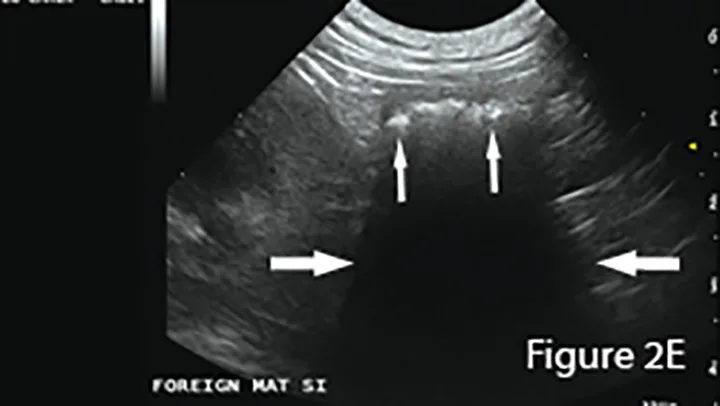

Ultrasound of small intestinal foreign material typically appears hyperechoic (small arrows) with strongly distal acoustic shadowing (large arrows), although this can vary depending on composition, shape, and number. Foreign material will not change shape with peristalsis and often has an organized surface for differentiation from intraluminal gas, which typically causes reverberation artifacts (ie, comet tails).